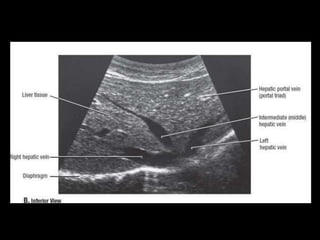

• US: Primeiro exame pedido ao: 1) dor no

hipocondrio direito; 2) testes de função

hepáticas anormais; 3) suspeita de

malignidade.

Técnicas de Imagem •US: Primeiro exame pedido ao: 1) dor no hipocondrio direito; 2) testes de função hepáticas anormais; 3) suspeita de malignidade. • TC: Tres fases – Arterial (10 a 20 segundos) – Fase venosa portal ( 30 segundos ) – Fase venosa hepática (60 segundos) • TC Portografia: Metastases.